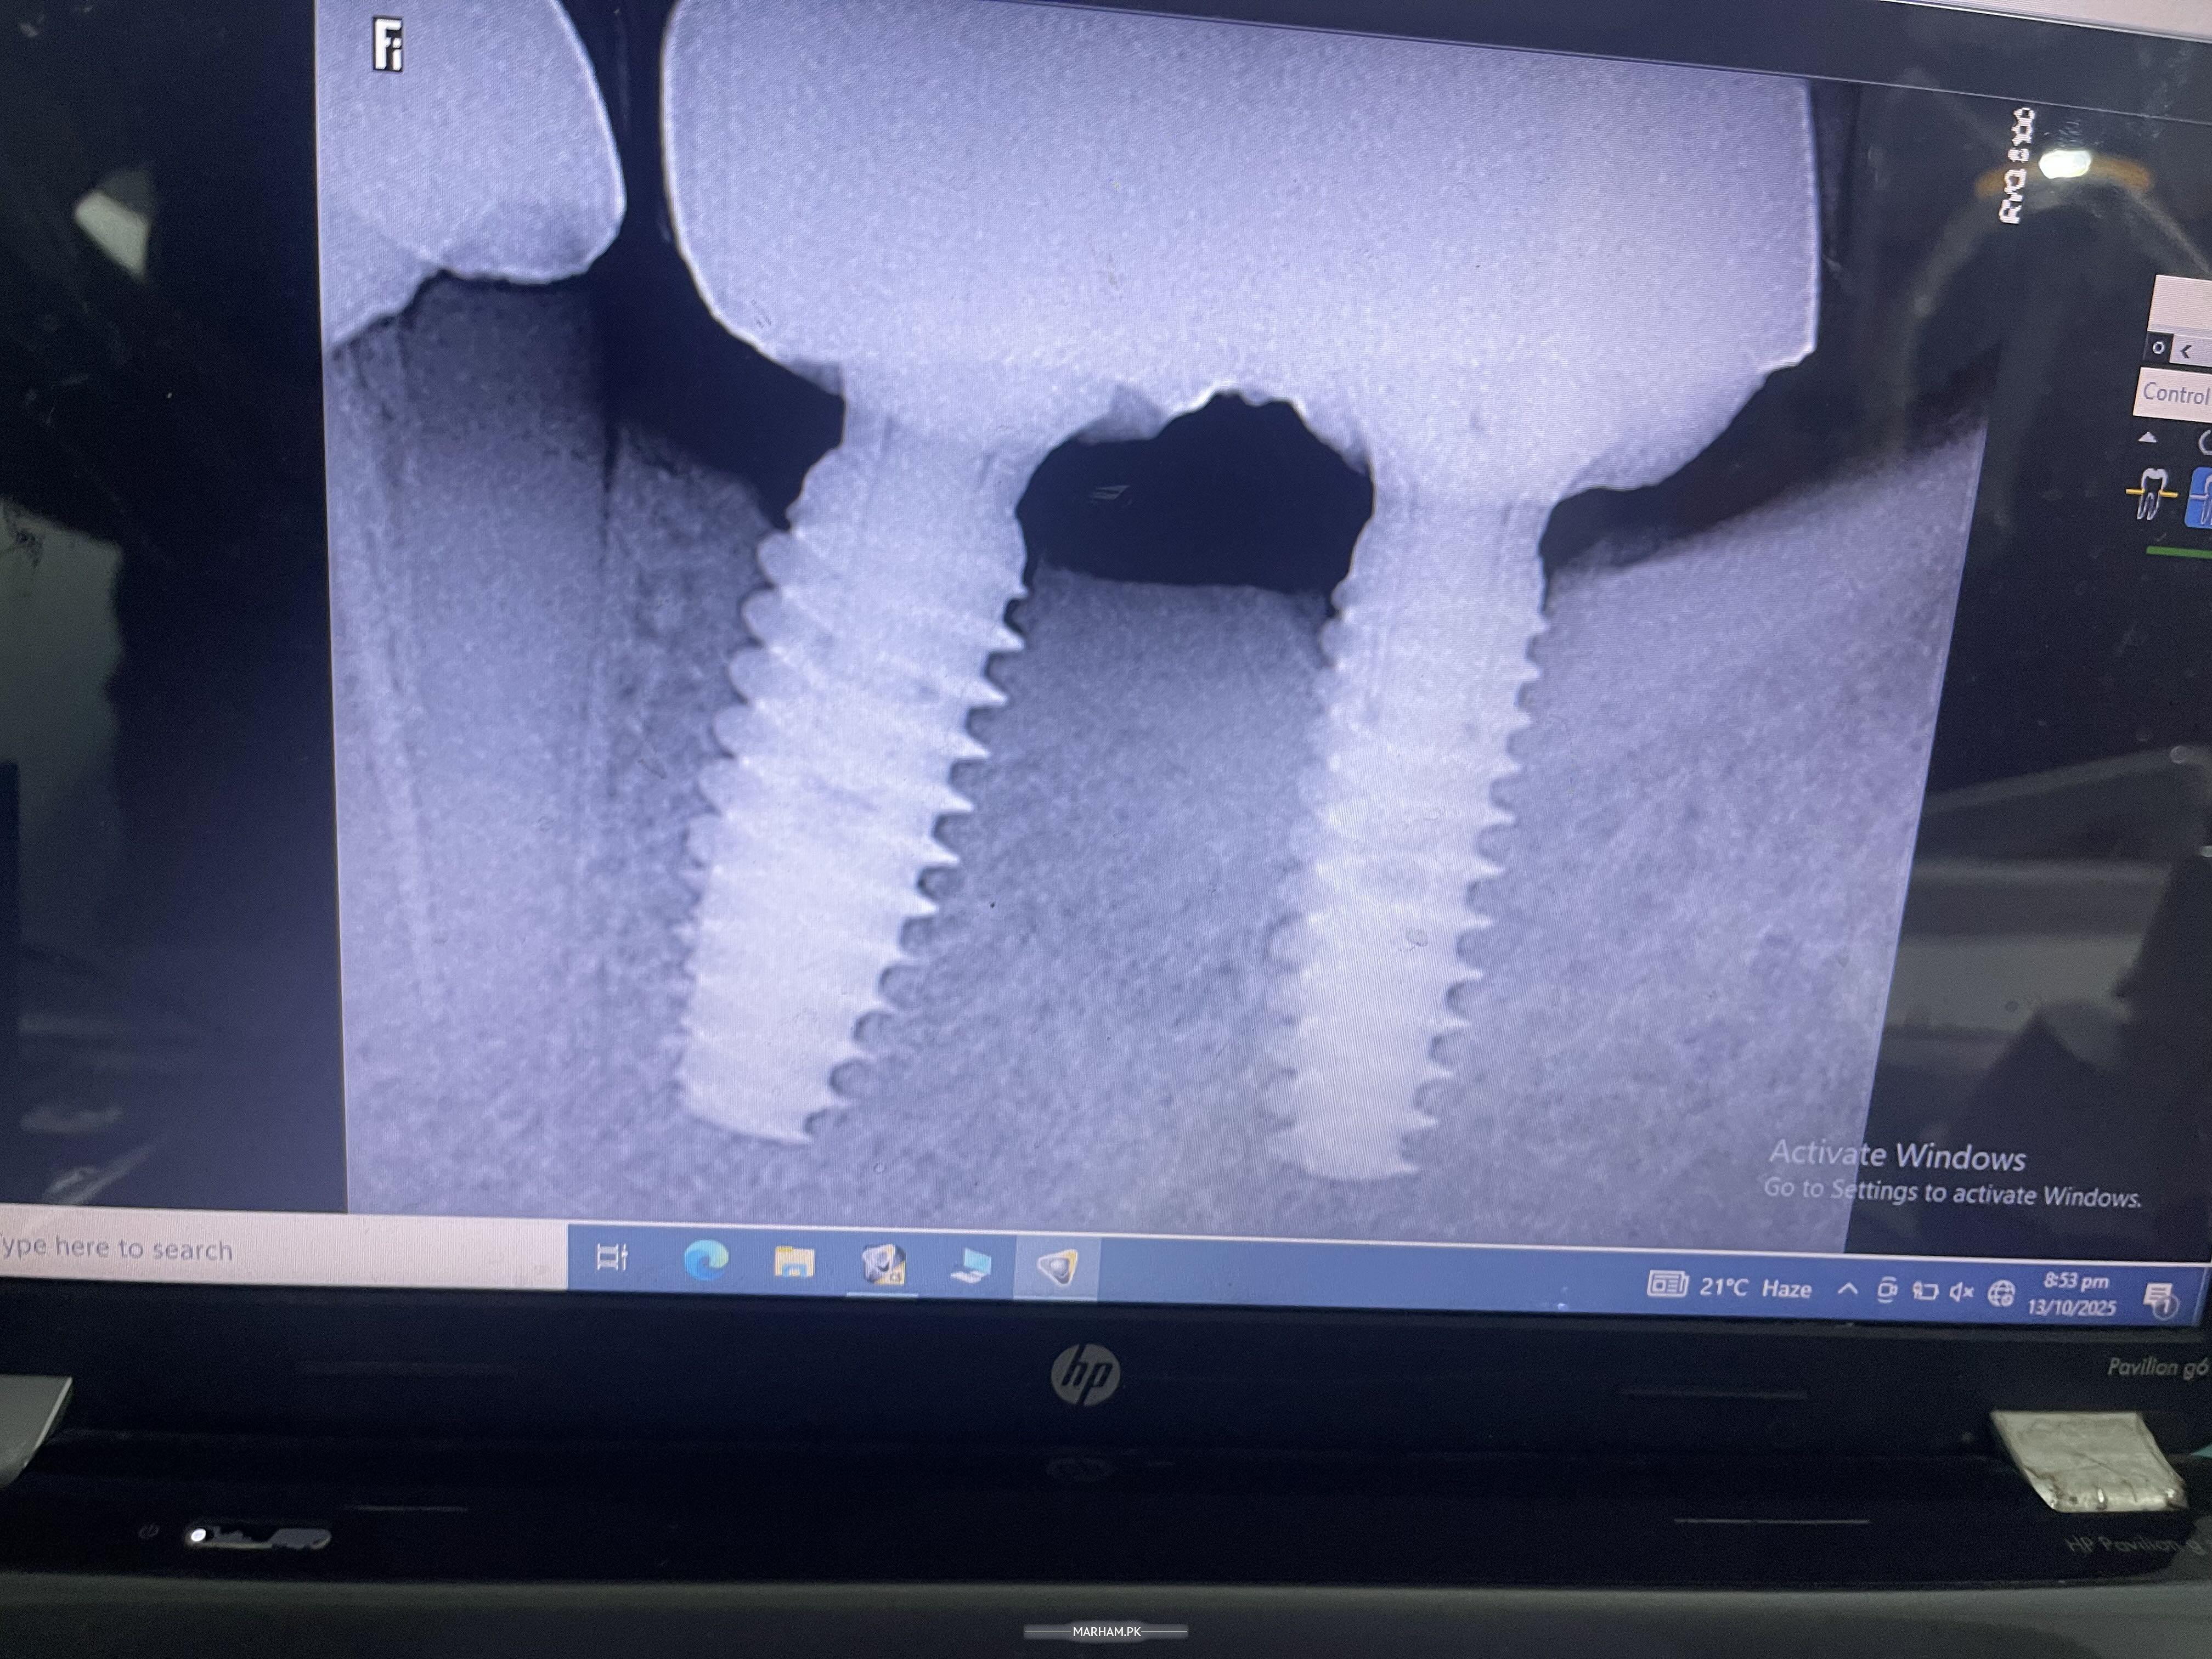

Attach Photo here: